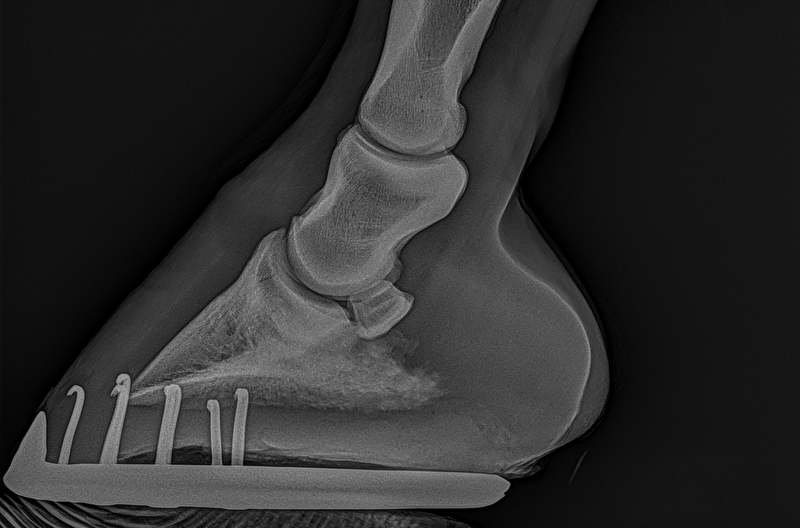

Insups schreef:Ik heb in 2022 een paard gekocht en volledig laten keuren. Die was door dierenarts 1 volledig in orde verklaard. Nu worden er nieuwe foto's gemaakt en blijkt hier toch een opmerking te zijn... Puur uit interesse ben ik benieuwd naar wat jullie zien